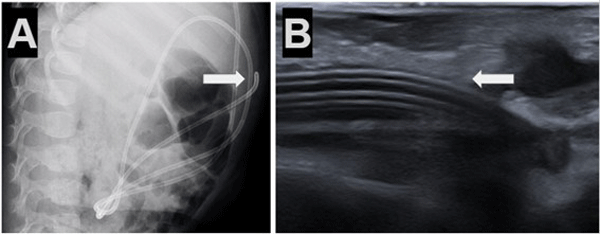

Caso 4. Paciente femenina de 10 años con antecedentes de nacimiento prematuro, hidrocefalia congénita y colocación DVP al mes de vida. Consultó por cuadro de cefalea y vómitos, tomografía de cerebro simple evidenció mayor tamaño ventricular en comparación con estudios previos. Radiografía de sistema mostró catéter distal fuera de la cavidad peritoneal (Figura 4).

Figura 4. Caso 4: A) Se observa Rx de tórax y abdomen (frente) con catéter distal a nivel abdominal con migración retrógrada. B) Magnificación de Rx de abdomen que evidencia catéter en doble caño con signo radiológico del “caño de escopeta” o “signo del anzuelo” (flecha blanca).

Caso 5. Paciente femenina de 1 año con antecedente de tumor de fosa posterior e hidrocefalia tratada con DVP al mes de vida, presentó episodios de vómitos y somnolencia con dilatación del sistema ventricular en comparación con estudios previos por tomografía simple de cerebro. Radiografías de sistema confirmaron migración subcutánea y retrógrada del catéter distal (Figura 5).

Figura 5. Caso 5: A) Se observa Rx de tórax y abdomen (perfil) con catéter distal a nivel abdominal con migración retrógrada. B) Ecografía abdominal: muestra ingreso y salida de catéter distal por mismo sitio; imagen típica de catéter en “doble caño” con signo ecográfico “caño de escopeta” (flecha blanca).